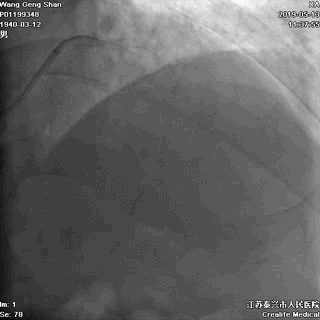

06 LM-LAD支架后扩张

交换回旋支导丝,非顺应性球囊顺序高压扩张

07 LM支架近段优化(POT)

左主干近段用大一号非顺应性球囊行高压扩张

IVUS评估,支架贴壁良好。